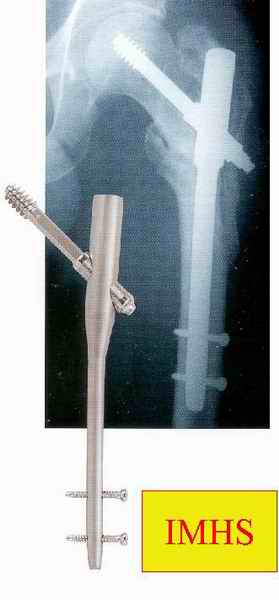

Большие преимущества у интрамедуллярных штифтов, метод хорош и можно произвести из минимального доступа, но во время операции необходимо контролирование варуса, затем приступить к блокированию.

слайды:

Long TFN

Short TFN

IMHS

DePuy Trochanteric Nail